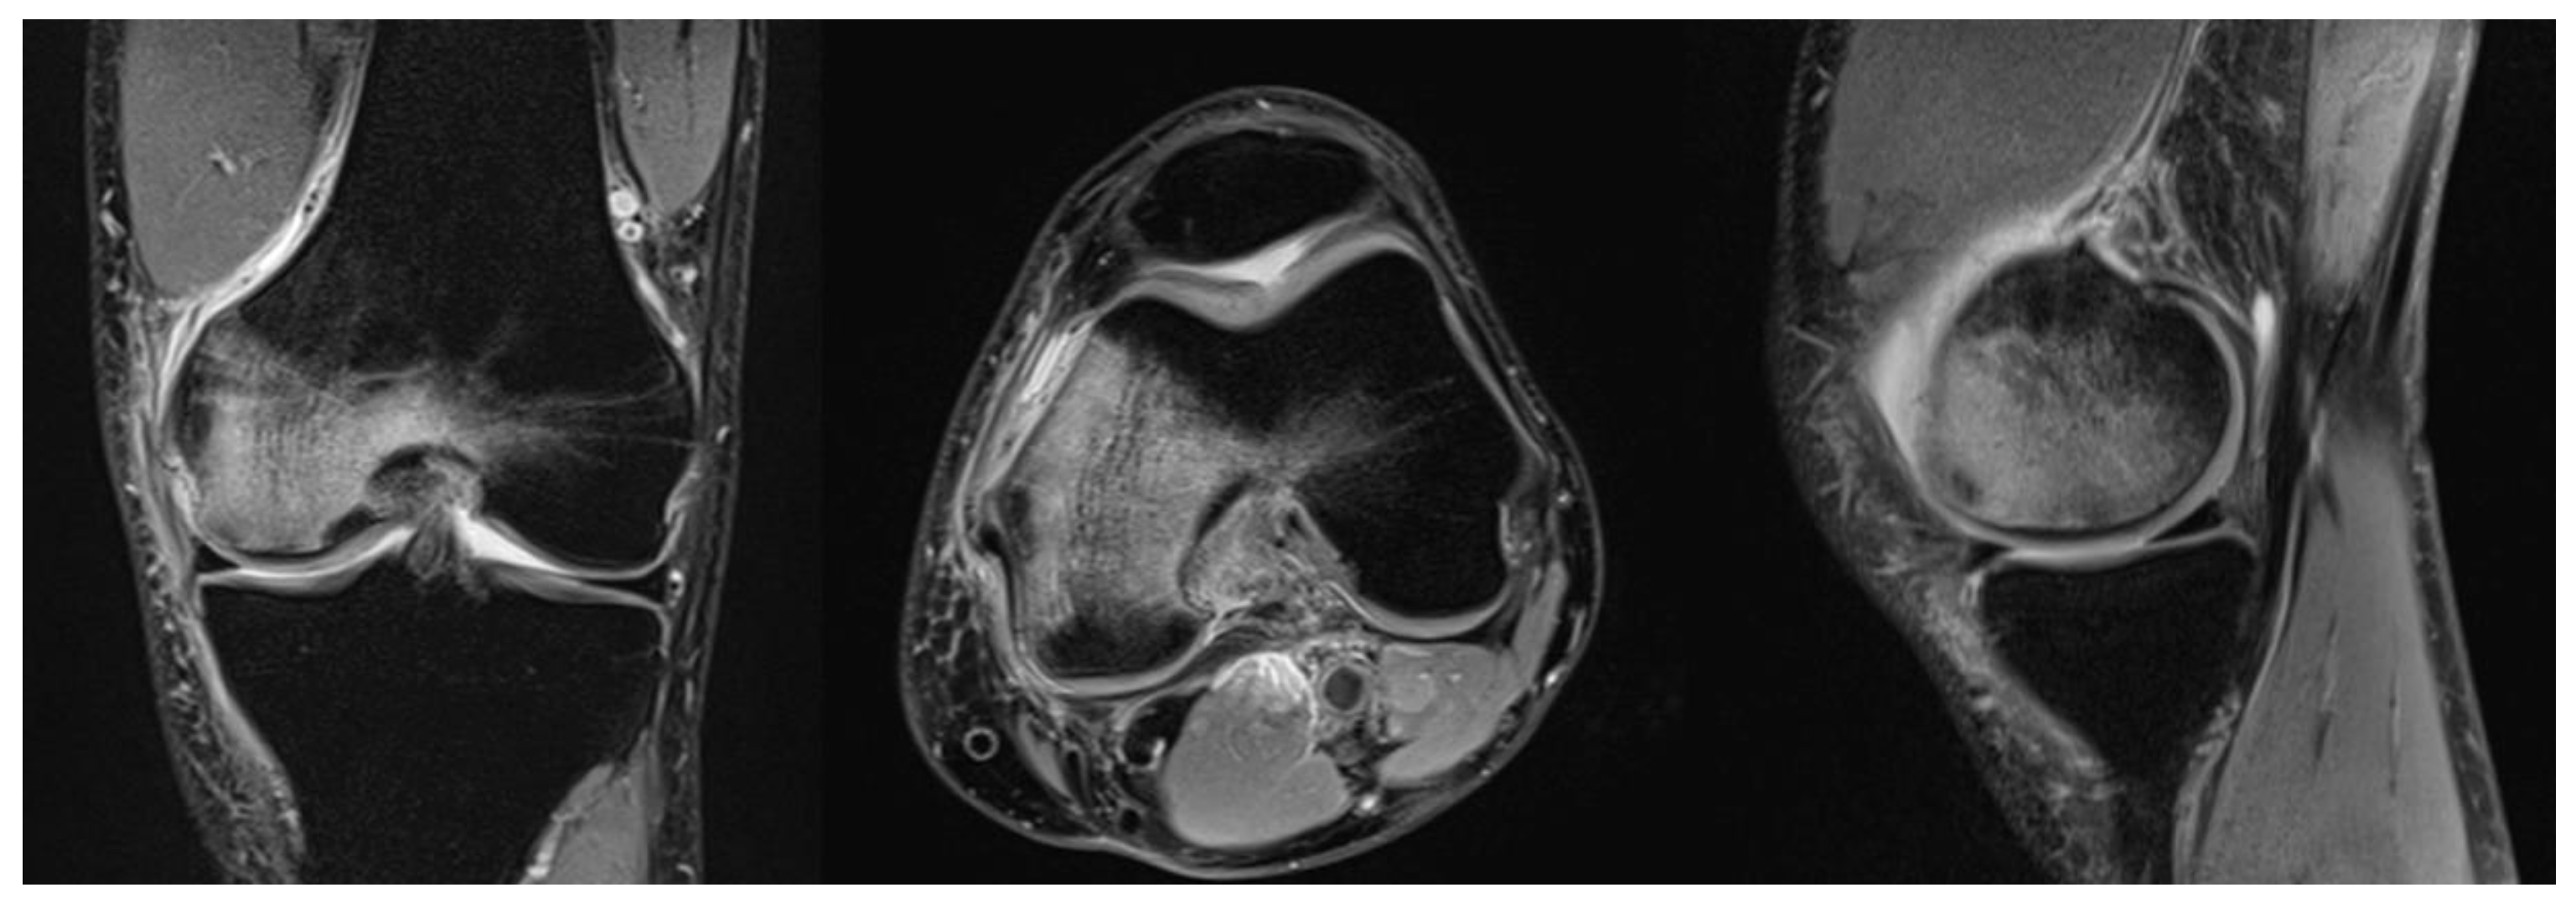

Because of its inherently high sensitivity, MRI is useful in the early stages of both SPONK and secondary ON. As bone oedema is presented from the early onset of the disease, these features are picked up on the MRI with high accuracy. On T1 images, features suggestive of osteonecrosis are low signal changes in the subchondral area in the affected condyle [32]. Typically, a crescentic fracture line may/can appear (in the images). These appearances were initially described in the hip and have now been identified and studied in osteonecrosis of the knee [15]. On T2-weighted images, the affected area has a margin of high signal changes [10] (Figure 1).

MRI is useful in confirming the size of the lesion initially measured on the X-ray by assessing parameters of width, depth and height of the lesion in the coronal and sagittal sections of the MRI [10].

Figure 1. MRI of a right knee in a 51-year-old man showing osteonecrosis of the femoral condyle.